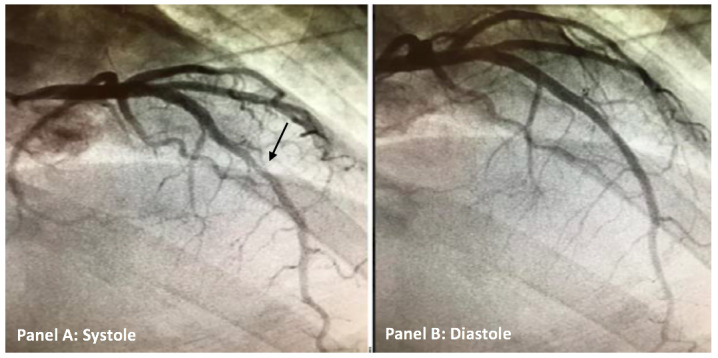

A myocardial bridge has traditionally been considered a benign condition characterized by an atypical intramyocardial route of a segment of one of the major coronary arteries. However, the clinical complications of myocardial bridges can be dangerous. These potential complications include acute coronary syndromes, arrhythmias, ventricular dysfunction, and sudden death. Myocardial bridges are suspected to be adjuvant of Kounis syndrome, which is defined as an acute coronary syndrome caused by an allergic reaction. Due to high epidemiologic prevalence, clinical suspicion of a myocardial bridge should be considered in atypical and typical presentations of chest pain, especially in patients with low-risk factors for atherosclerotic disease. A male in their late 30's presented with non-ST elevation myocardial infarction suspected to be secondary to Kounis syndrome after gadobenate dimeglumine contrast media was used for an imaging study. His clinical presentation was further complicated when he was found to have a mid-left anterior descending coronary artery myocardial bridge.